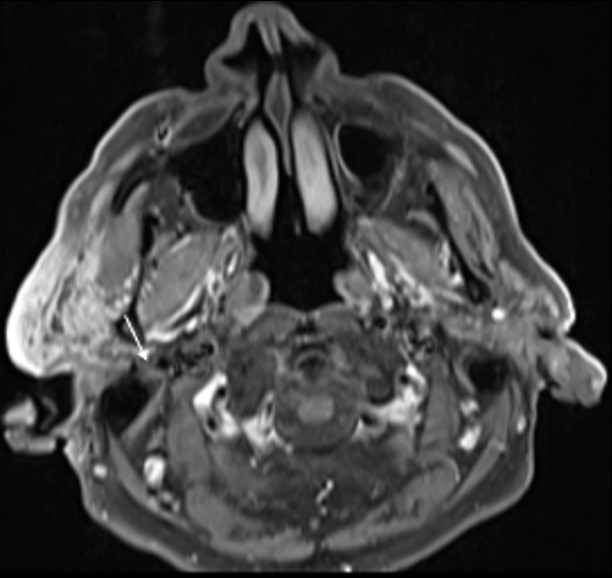

The lesion also revealed restricted diffusion, with an ADC value of 0,858 x 10-3 mm2/s (Fig. 4). Additionally, a more focal nodular and irregular area was evident in the superficial parotid lobe. There was also a noticeable infiltration of the adjacent fat planes and skin, invasion of the right masseter muscle, and extension of the lesion to the submandibular space without the involvement of the right submandibular gland (both submandibular glands were atrophic). The right facial nerve showed a moderate high signal on T2-weighted images and post-contrast hyperenhancement that was perceptible in its path up to the stylomastoid foramen, which was a cause of concern regarding perineural spread (Fig. 5). Retromandibular vein thrombosis was visible. An increased number of lymph nodes was present in all right cervical levels, the largest node measuring 11 mm (in greater diameter), some of them showing round morphology and central areas of necrosis. There were no signs of mandibular invasion or other suspicious bone lesions. CT also excluded signs of lung metastases. Ultrasound-guided fine needle aspiration of the right parotid lesion was performed, demonstrating involvement of the parotid parenchyma by a malignant tumor with a nest pattern constituted by epithelioid cells with eosinophilic cytoplasm and atypical nuclei, with evident nucleolus and frequent mitoses. Comedonecrosis-type tumor necrosis areas, as well as lymphatic and vascular invasion were observed. The findings were compatible with a salivary duct carcinoma (SDC), with expression of androgen receptors. The management options were discussed in a multidisciplinary group meeting and with the patient. Due to the extension of the neoplastic lesion and the potential morbidity associated with the surgical procedure that would preclude a complete resection, radiotherapy and antiandrogen therapy were chosen.